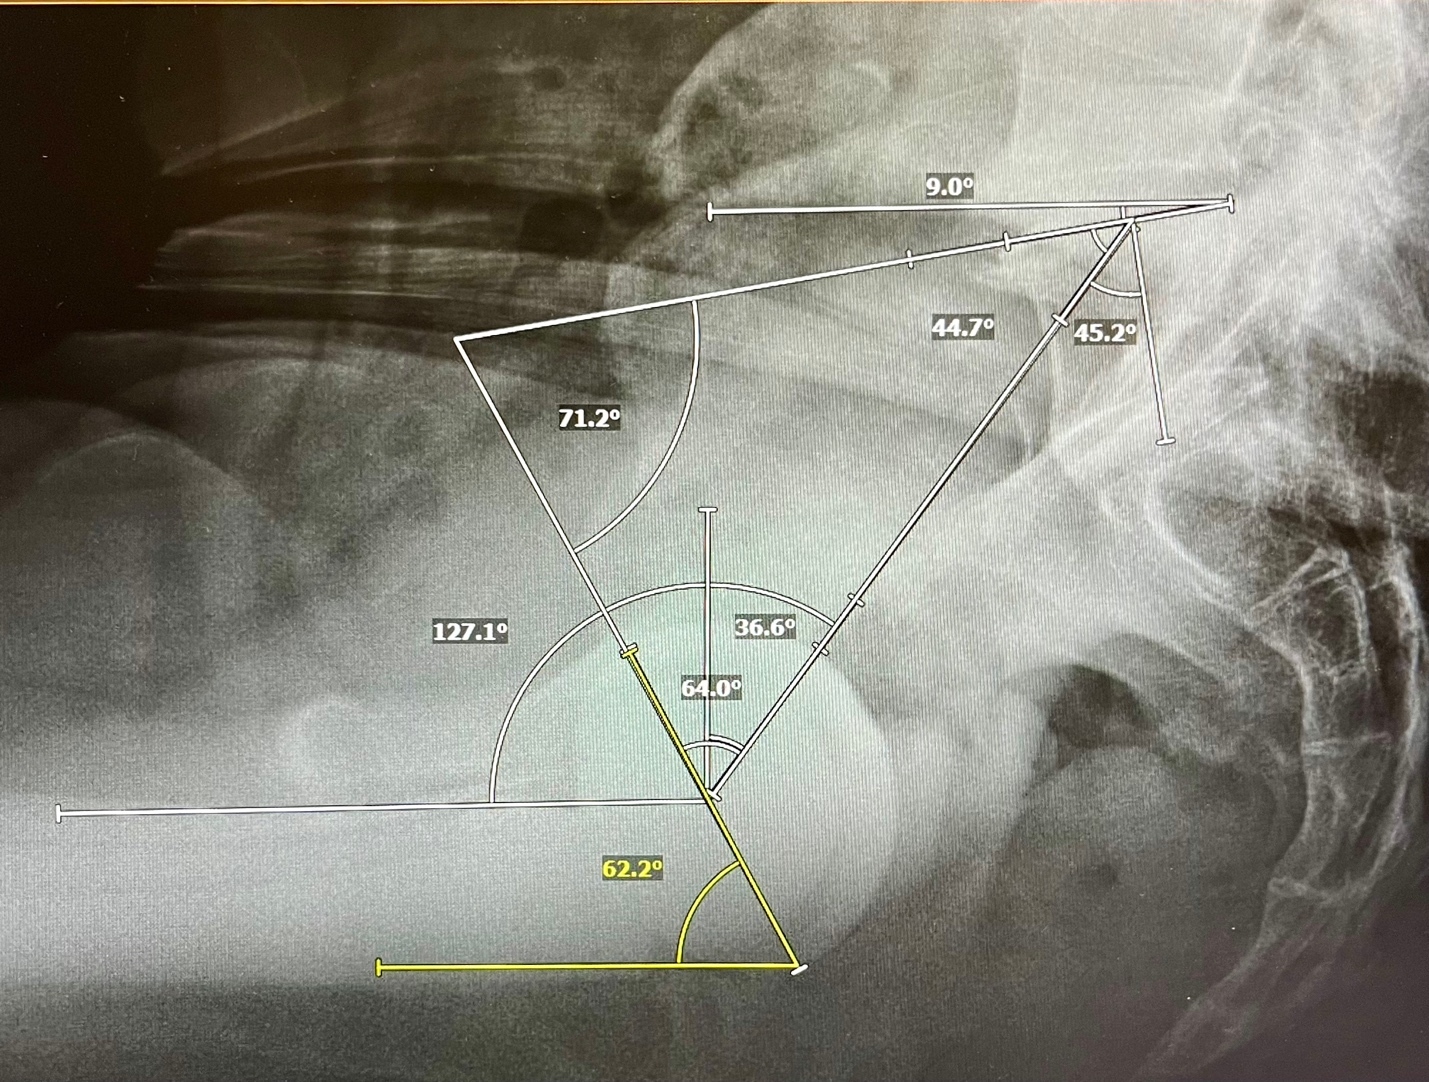

This is a descriptive mathematical study of the sagittal plane functional mechanics of the spinopelvic postural system including a hemispherical acetabular component. The cup may be incorporated into the spinopelvic system using a triangular parameter construct created by combining 2 known angular equations. Firstly, the pelvic parameters are related by the equation defining Pelvic Incidence, PI, a morphologic and functional descriptor of pelvic construction (Legaye et al. 1998). Algebraically, the constant PI equals the sum of the reciprocal functional parameters SS and PT as PI=SS+PT. The acetabular parameters are related by the equation defining the Sacroacetabular Angle of Lazennec, (SAA), as SAA=SS+AI (Lazennec et al. 2004). Superimposing these 2 equations on the sagittal plane of the pelvis reveals the central triangular structure, (Figure 1) connecting three points in space, the anatomic hip and S1 endplate centers and the SAA angle vertex at the intersection of the cup AI tangent line and the SS line (Bodner 2022). The 3 angles created inside this triangle are the anatomically fixed apex angle of (90°-PI), the SAA angle and at the hip joint itself, the Pelvic Acetabular Angle, (PAA), relating the AI cup angle to the PT angle in a similar fashion as the SAA relates the cup to the SS angle. In any individual, SAA and PAA behave reciprocally just as their underlying constituents, SS and PT do. The hip joint combined flexion/extension parameter, Pelvic Femoral Angle, PFA, is measured from S1 center to hip center then continuing parallel to the anterior femoral cortex towards the knee center (Ike et al. 2018).

There are 5 angles with their apices at the hip joint that may be analyzed for individualized cup planning or understanding alterations caused by spinal realignment (Figure 2). From superior to inferior, they are PT, (90°-AI), PAA, AI, and PFA. Involuntarily modulating PT represents the body’s main mechanism to balance the trunk and head as they incline forward with aging and deterioration (Barrey et al. 2013; Diebo et al. 2015). PFA represents the collective orientations of the PT angle above and the femoral shaft angle below the hip center, it is intimately correlated to the truncal inclination parameter, the T1 Pelvic Angle, (TPA), thus PFA reactively counterbalances the sagittal spinal imbalance above the hip through flexion/extension of the joint itself (Hasagawa et al. 2016). Adding the calculated AI to the PFA in standing and sitting gives the validated functional safe zone parameter for both acute and chronic dislocation, Combined Sagittal Index, CSI (Heckmann et al. 2018; Grammatopoulos et al. 2022). PAA is algebraically the sum of (90-AI) + PT, the complementary angle to AI is necessary as a consequence of PT being vertically referenced.

The full sequence of determining biomechanically optimal acetabular parameters, including cup AI, (AI-PT), PAA, and the CSI using PI/PT/PFA preoperative measurements is illustrated in Figure 4, column A.

Measure patient PI, PT, PFA stand/ sitting: PI 60, PT 27/42, delta SS= 15°, PFA 196/129

Compare PT standing to normative PT for PI 60: 27 vs 15, a +12° PT variance

Apply 4:1 Tilt correction:

+12° PT correction= +3° standing AI correction (Rule of 4s) from normative AI of 30°= 33° AI standing

(AI-PT) standing correction = -0.75 x 12= 9° Normative for PI 60= (30-15) =15° 15-9= 6°

Mobility correction:

- 10° stiffness correction from neutral 25° to measured 15° dSS applies +5° to standing AI, -5° to sitting AI, +5° to (AI-PT). Therefore, the targeted AI becomes 38/53° stand/sit, (AI-PT) becomes 11° making SAA 60+11=71° and PAA 90-11=79°. Sitting (AI-PT) confirms (53-42)=11°.

CSI calculation: CSI=AI+PFA stand/sit. Standing limit <244° for posterior impingement, >151° for anterior impingement

Stand- 38+196=234°, Sit- 53+129=182°, this cup is safe within limits.